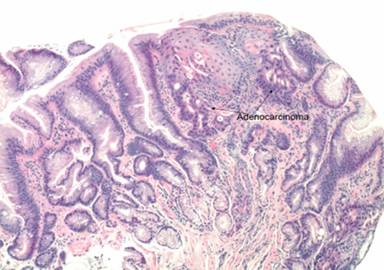

A 70-year-old Caucasian man presented with abdominal distention, weight loss, icterus, along with intermittent nausea and vomiting. He was a lifetime non-smoker, and had history of only moderate alcohol use. Three years prior, the patient had undergone minimally invasive esophagogastrectomy for a stage I adenocarcinoma of the gastroesophageal junction (Figure 1), likely arising in a long-standing Barrett’s esophagus. Serial esophagogastroduodenoscopies and computed tomography (CT) scans since that time had shown no evidence of residual or recurrent disease. Serial CEA and CA 19-9 levels were also within normal limits, and the esophageal cancer was deemed successfully eradicated.

Figure 1. Microphotograph showing adenocarcinoma (arrows) of the esophagus (H&E, 4x magnification). |